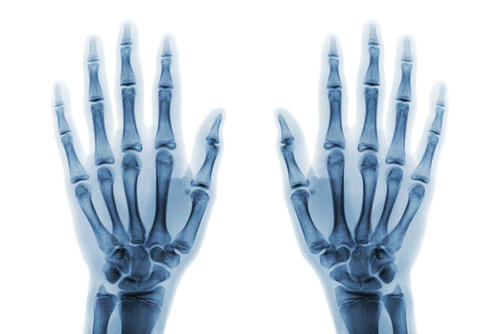

Рентгенография актуальна для диагностики ревматоидного артрита, артроза, вывиха, разрыва связочного аппарата, трещины костей, перелома костных структур, гнойных процессов. Рентген-снимок кисти информативен в плане обнаружения онкологических процессов, доброкачественных опухолей, воспалительных заболеваний, кист, остеопороза, патологий мышц и лимфатических узлов, остеофитов, кальцификатов.